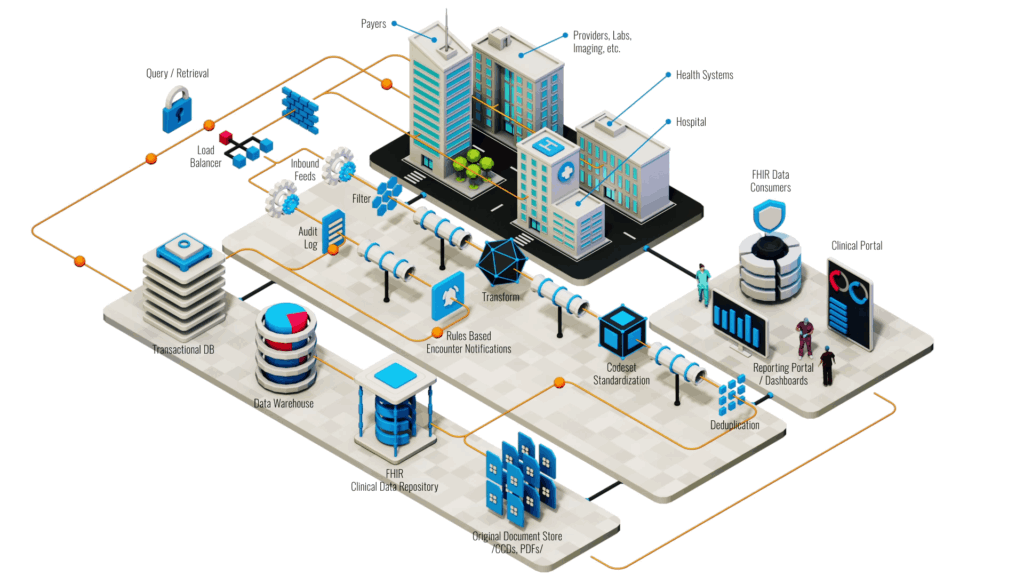

HL7 messaging and Interoperability

HL7 interoperability refers to the ability of healthcare information systems to communicate and exchange data seamlessly using the HL7 (Health Level 7) standards. HL7 is a set of international standards for the exchange, integration, sharing, and retrieval of electronic health information.

Interoperability ensures that different healthcare systems, such as electronic health records (EHRs), laboratory information systems (LIS), radiology information systems (RIS), and others, can communicate effectively and share patient data accurately.

Mirth Connect is an open-source integration engine designed for healthcare, enabling seamless data exchange between healthcare systems using various messaging standards like HL7, FHIR, and DICOM. It provides tools for transforming, routing, and monitoring messages.

Salient Features

- Seamless Data Exchange

- Enhanced Efficiency

- Improved Coordination

Interoperability

- Hopital Info Systems

- RIS Info Systems

- LIS info Systems

- EHR / EMR Systems